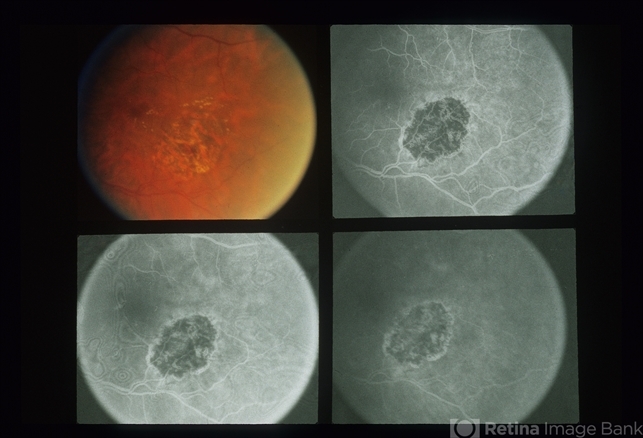

Branch Vein Occlusion (BVO)

Branch Vein Occlusion

Seventy one year old white female, 20/50 OU.